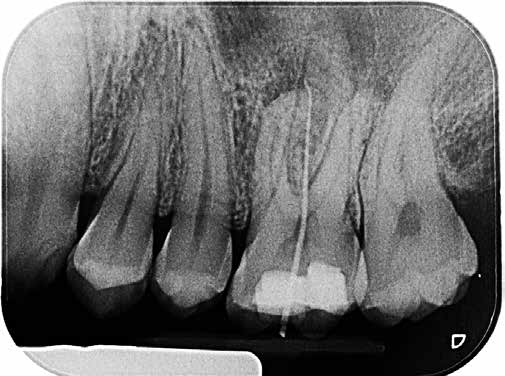

Als sich der Patient immer noch schmerzfrei 4 Wochen später im Rahmen des Termins zur definitiven Versorgung in der Praxis vorstellte, war lediglich noch das Fistelmaul, aber keine Erhebung am Zahnfleisch mehr zu sehen (Abb. 4). Nachdem auch sonst keine Auffälligkeiten festzustellen waren, wurde wie geplant mit der endgültigen Versorgung des Zahnes 26 begonnen. Hierfür wurde zunächst eine Isolierung des Zahnes mit Kofferdam vorgenommen (Abb. 5). Für ein genaueres Bild vom Verlauf der Wurzelkanalanatomie lieferte eine Kontrastaufnahme mithilfe von K-Feilen und eines Silberstiftes, mb2, (Abb. 6) die notwendigen Informationen. Dabei stellte sich heraus, dass insbesondere einer der Kanäle sich durch eine außerordentliche Krümmung von beinahe 90° auszeichnete (Abb. 7).

Aus diesem Grund fiel die Wahl für die sich anschließende Aufbereitung auf ein Feilensystem mit besonders hoher Flexibilität und Festigkeit (WaveOne Gold, Dentsply Sirona). Vor der eigentlichen Aufbereitung erfolgte das Anlegen eines Gleitpfads mit geeigneten Gleitpfadfeilen für stark gekrümmte Kanäle (PathFile, Dentsply Sirona) mit einem weniger starken Taper (02) in aufsteigender Größe (ISO 13, 16 und 19). Die Aufbereitung wurde im Anschluss mit der Primary-Feile (rot 25/07) sowie der Medium-Feile (grün 35/06) des Feilensystems vorgenommen. Jedem Feilengang schloss sich dabei eine gründliche Spülung anhand eines gängigen Spülprotokolls an.

Nach der Aufbereitung wurden die Wurzelkanäle mit zum Feilensystem passenden Guttapercha-Mastercones (Conform Fit Technologie) bestückt. Ihr einwandfreier Sitz im Kanal ließ sich mithilfe einer Masterpointaufnahme kontrollieren (Abb. 8). Mithilfe warmvertikaler Kompaktion konnten die Wurzelkanäle danach gefüllt werden (Abb. 9). Aufschluss über die Passung dieser Füllung gab eine Backfill-Aufnahme (Abb. 10).